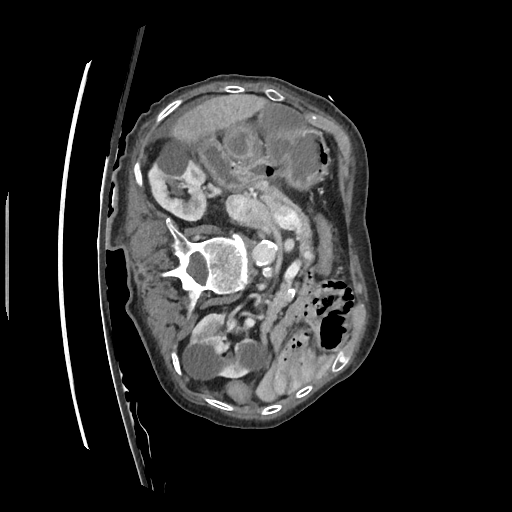

This challenge includes liver segmentation and liver tumor segmentation. The dataset consists of 131 training datasets and 70 testing datasets, all of which are 3D abdominal CT scan images that contain liver. Label maps (annotations) are provided for the training data, but not for the testing data. Participants are required to train their model on the training data, then use the well-trained model to make predictions for the testing data. The prediction can be submitted back to the orgnizer for blind evaluation. An example 3D CT data visualized in different directions is shown in Figure 5.

Refer to caption

Figure 5: Different positions of an example 3D CT data. Upper left: oblique coronal position. Upper right: add annotation (label) to the upper left image, where yellow area is the liver, green areas are the tumors on the liver. Lower left: sagittalia position; lower right: oblique-axial position.